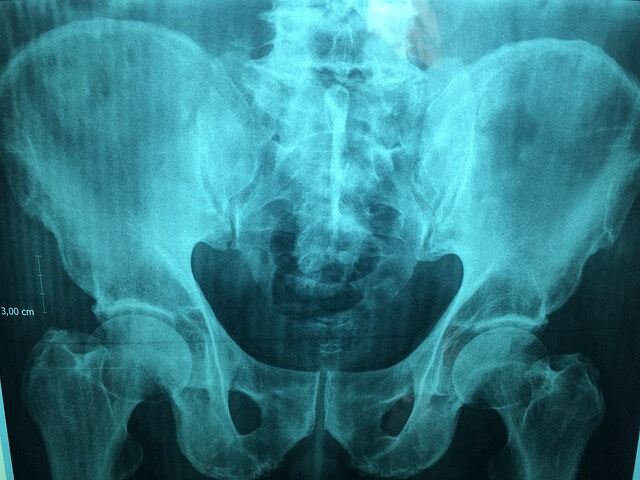

1. 치골이개란?

치골이개는 골반 앞쪽에 위치한 치골결합(symphysis pubis)이 비정상적으로 이완되거나 벌어지면서 통증을 유발하는 상태입니다. 치골결합은 왼쪽과 오른쪽 치골을 연결하는 섬유성 관절로, 정상적으로는 약간의 움직임만 허용됩니다. 하지만 임신 중에는 출산을 대비해 골반이 자연스럽게 이완되는데, 이 과정이 지나치면 치골이개로 이어질 수 있습니다.

정형외과, 산부인과, 재활의학과에서 초음파, MRI 등으로 진단이 가능하며, 약물치료, 물리치료, 체외충격파 치료 등이 시행될 수 있습니다.